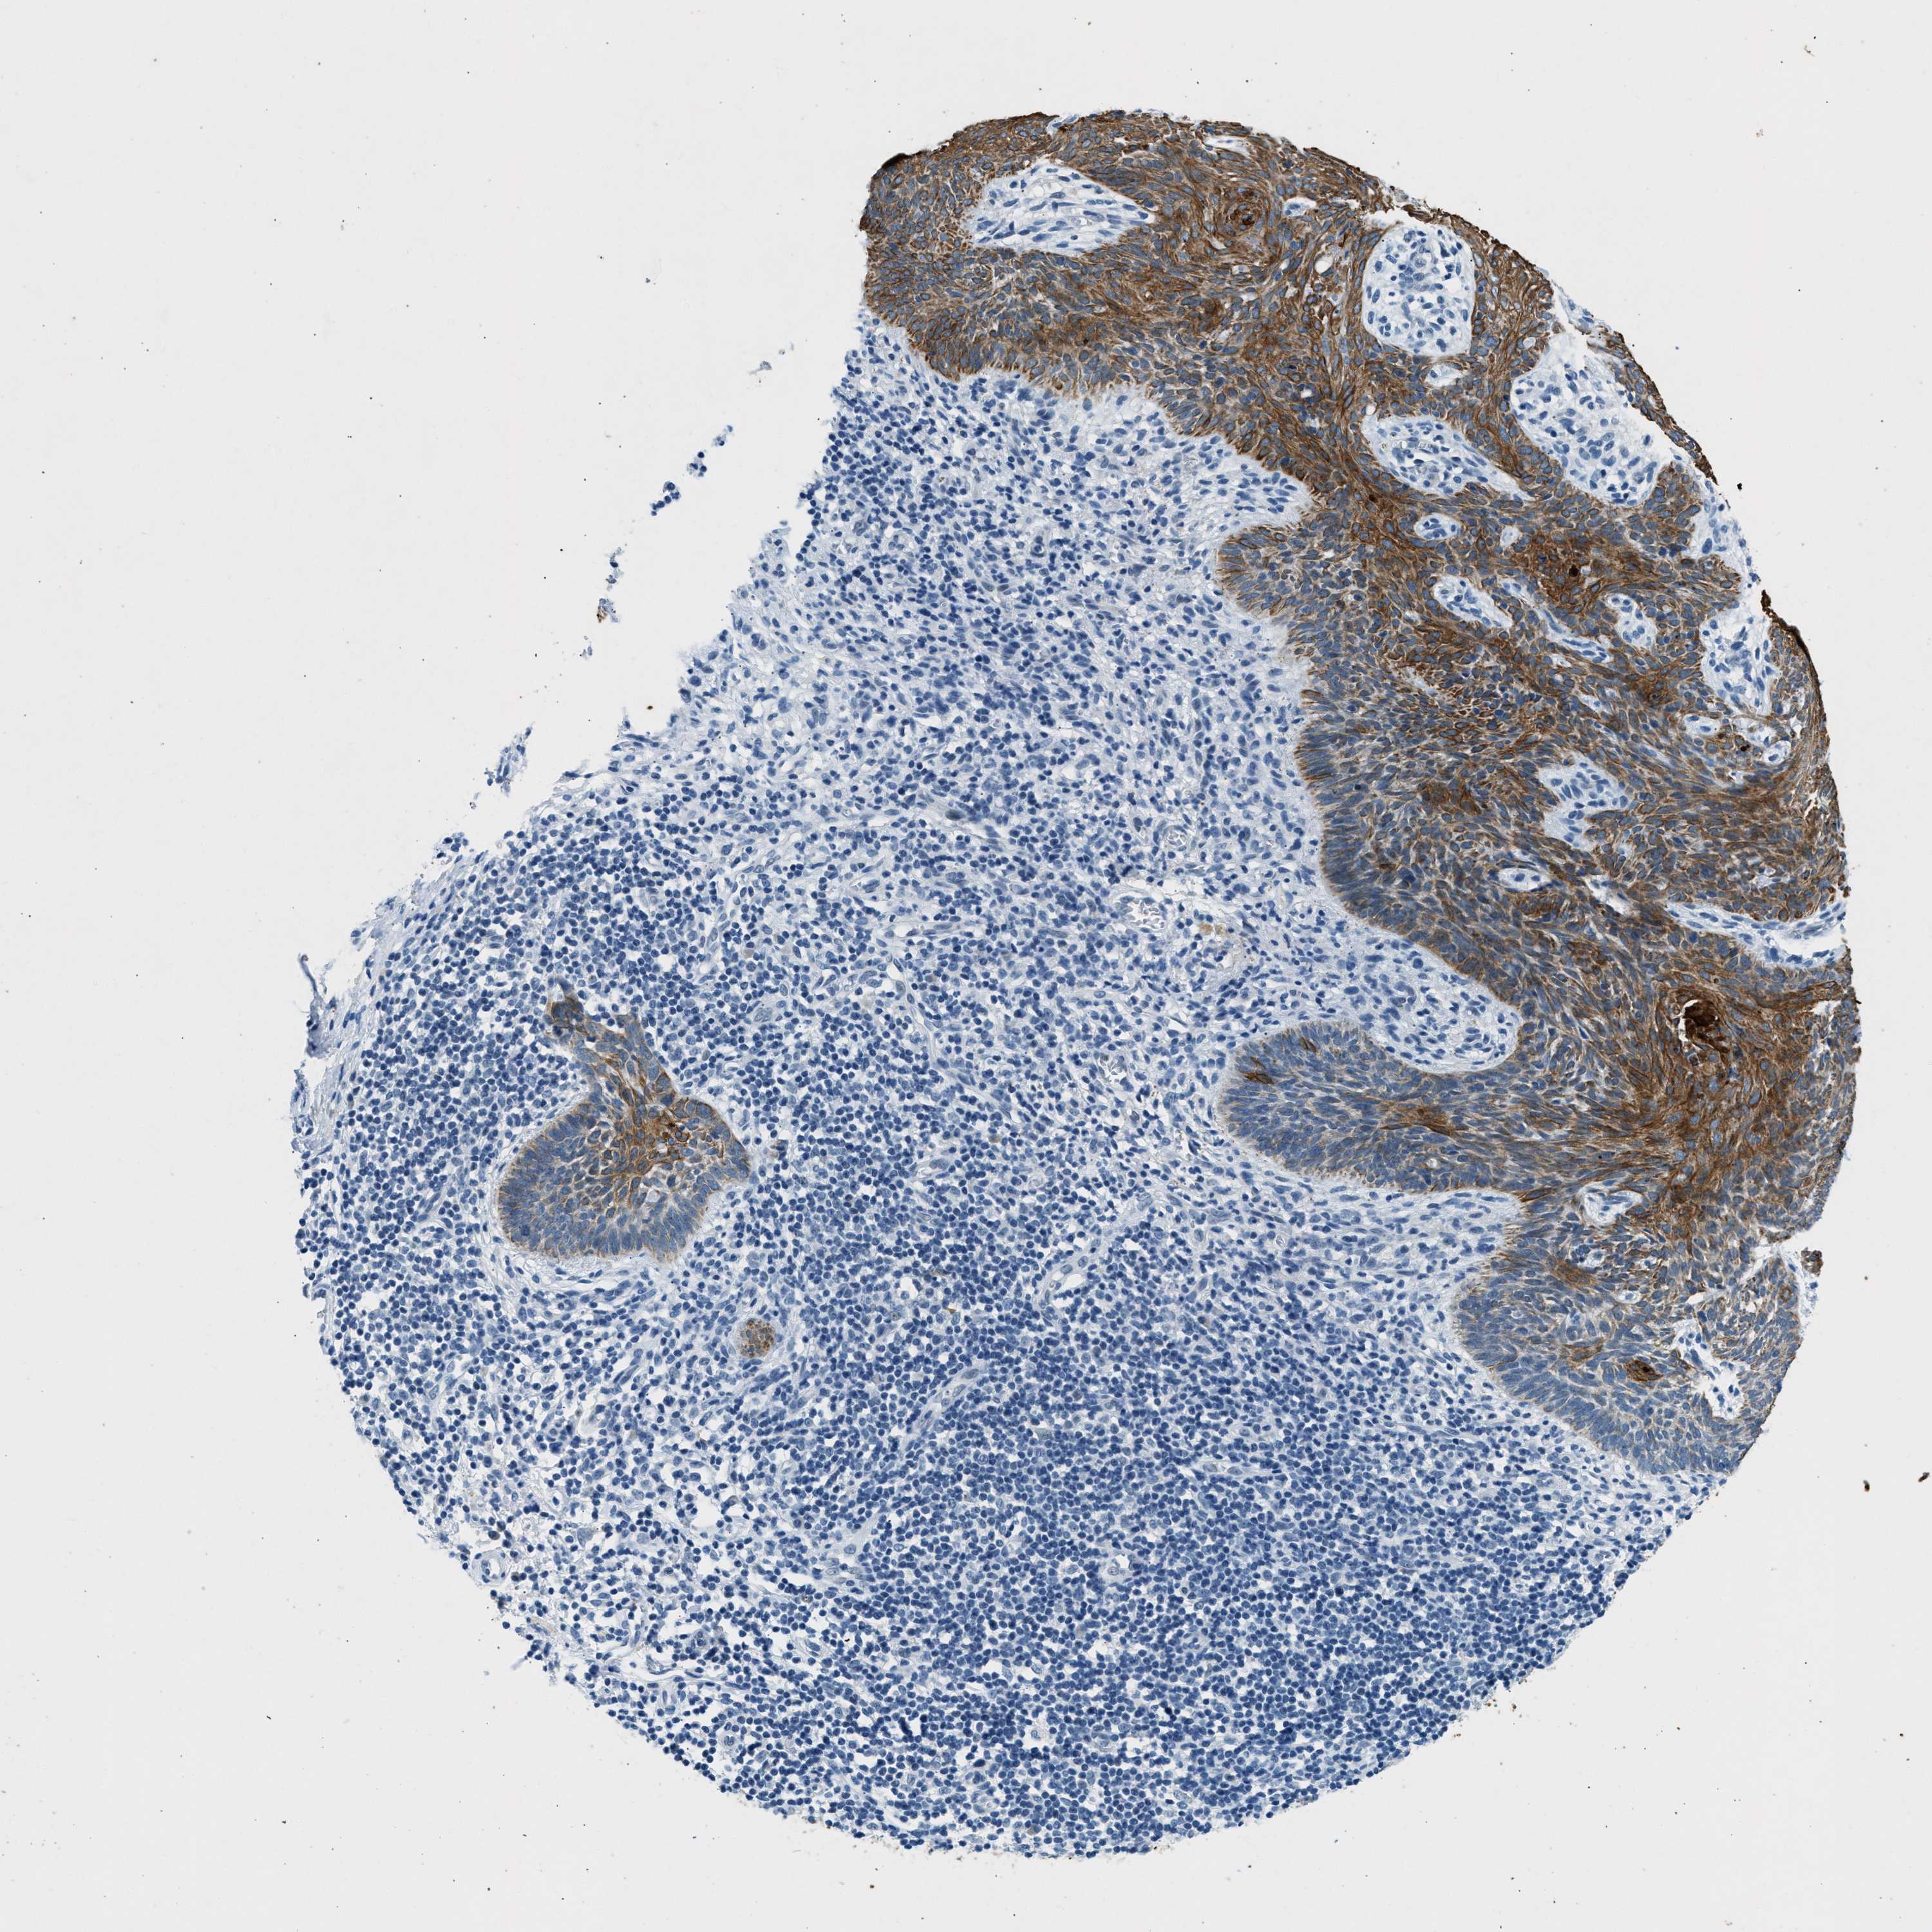

SKIN CANCER - Protein expressioni

A mouse-over function shows sample information and annotation data. Click on an image to view it in a full screen mode. Samples can be filtered based on level of antibody staining by selecting one or several of the following categories: high, medium, low and not detected. The assay and annotation is described here.

Antibody stainingi

Antibody staining in the annotated cell types in the current human tissue is reported as not detected, low, medium, or high, based on conventional immunohistochemistry profiling in selected tissues. This score is based on the combination of the staining intensity and fraction of stained cells.

Each image is clickable and will lead to virtual microscopy that enables deeper exploration of all samples and also displays staining intensity scores, fraction scores and subcellular localization as well as patient and tissue information for each sample.

Antibody HPA018195

Staining

High

Medium

Low

Not detected

Intensity

Strong

Moderate

Weak

Negative

Quantity

>75%

75%-25%

<25%

None

Location

Nuclear

Cytoplasmic/membranous

Cytoplasmic/membranous,nuclear

Squamous cell carcinoma, NOS